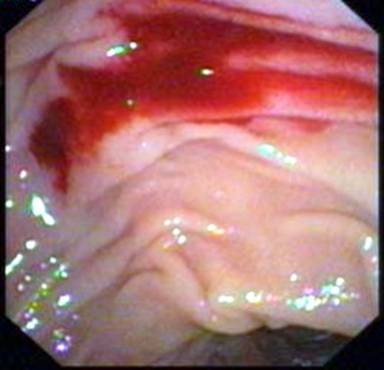

Capsule endoscopy (Given Imaging Ltd., Yoqneam, Israel) was performed after overnight fasting and preparation with polyethylene glycol ingestion and revealed the presence of fresh blood in the proximal jejunum along with a pool of fresh blood with no underlying ulcer (Figure 1). The major papilla was not identified on the capsule endoscopy. A push enteroscopy was subsequently performed which revealed the presence of fresh red blood in the distal duodenum and proximal jejunum. No bleeding lesion was identified. The push enteroscope was immediately withdrawn and a side viewing endoscope (TJF 160, Olympus Optical Co. Ltd., Tokyo, Japan) was inserted. On side view endoscopy, a pool of fresh blood was localized near the papilla (Figure 2). Using a cannula, the area was washed with distilled water and revealed an ooze of fresh blood from a pinpoint defect in the periampullary region. There was no surrounding ulcer or reddish area suggestive of a Dieulafoy’s lesion (Figure 3). Immediate hemostasis was achieved with an endoscopic injection of adrenalin.

Figure 2. Side view endoscope: fresh blood near the papilla. |